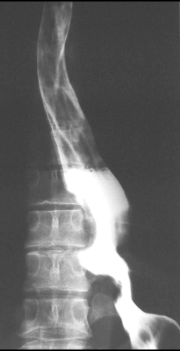

Leiomyome 1/3 inferieure de oesophge

: L lumiere de oesophge est redusent par une

refoulement reguliere de l muqueuse |

Image TDM : Masse homogene de

densite tissulire , non calcifie , hypervasculaire

et hyper T2 heterogene |